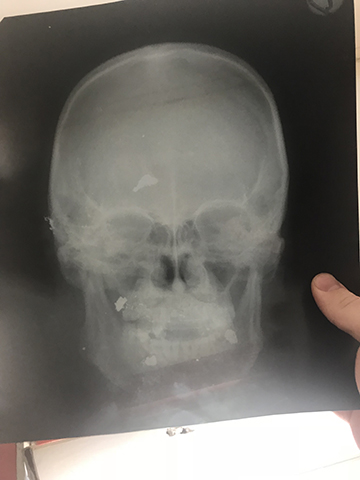

Our rounds finished, we may have time to see some patients in clinic prior to lunch. This requires a translator because a lot of patients won’t speak or understand French well enough, and the more common language is Lingala. For clinic, there isn’t even an attempt at a daily schedule or appointments. People arrive whenever, and then wait to see a doctor in order of arrival. Their medical charts are little notebooks that they carry with them any time they need to be seen! They then place these in order of arrival in a little hanger near my door. People come in with anything and everything. I recently saw a man who had been shot a month ago in a hunting accident and had shrapnel still imbedded in his face and brain! We had two head x-rays to confirm and that was all!